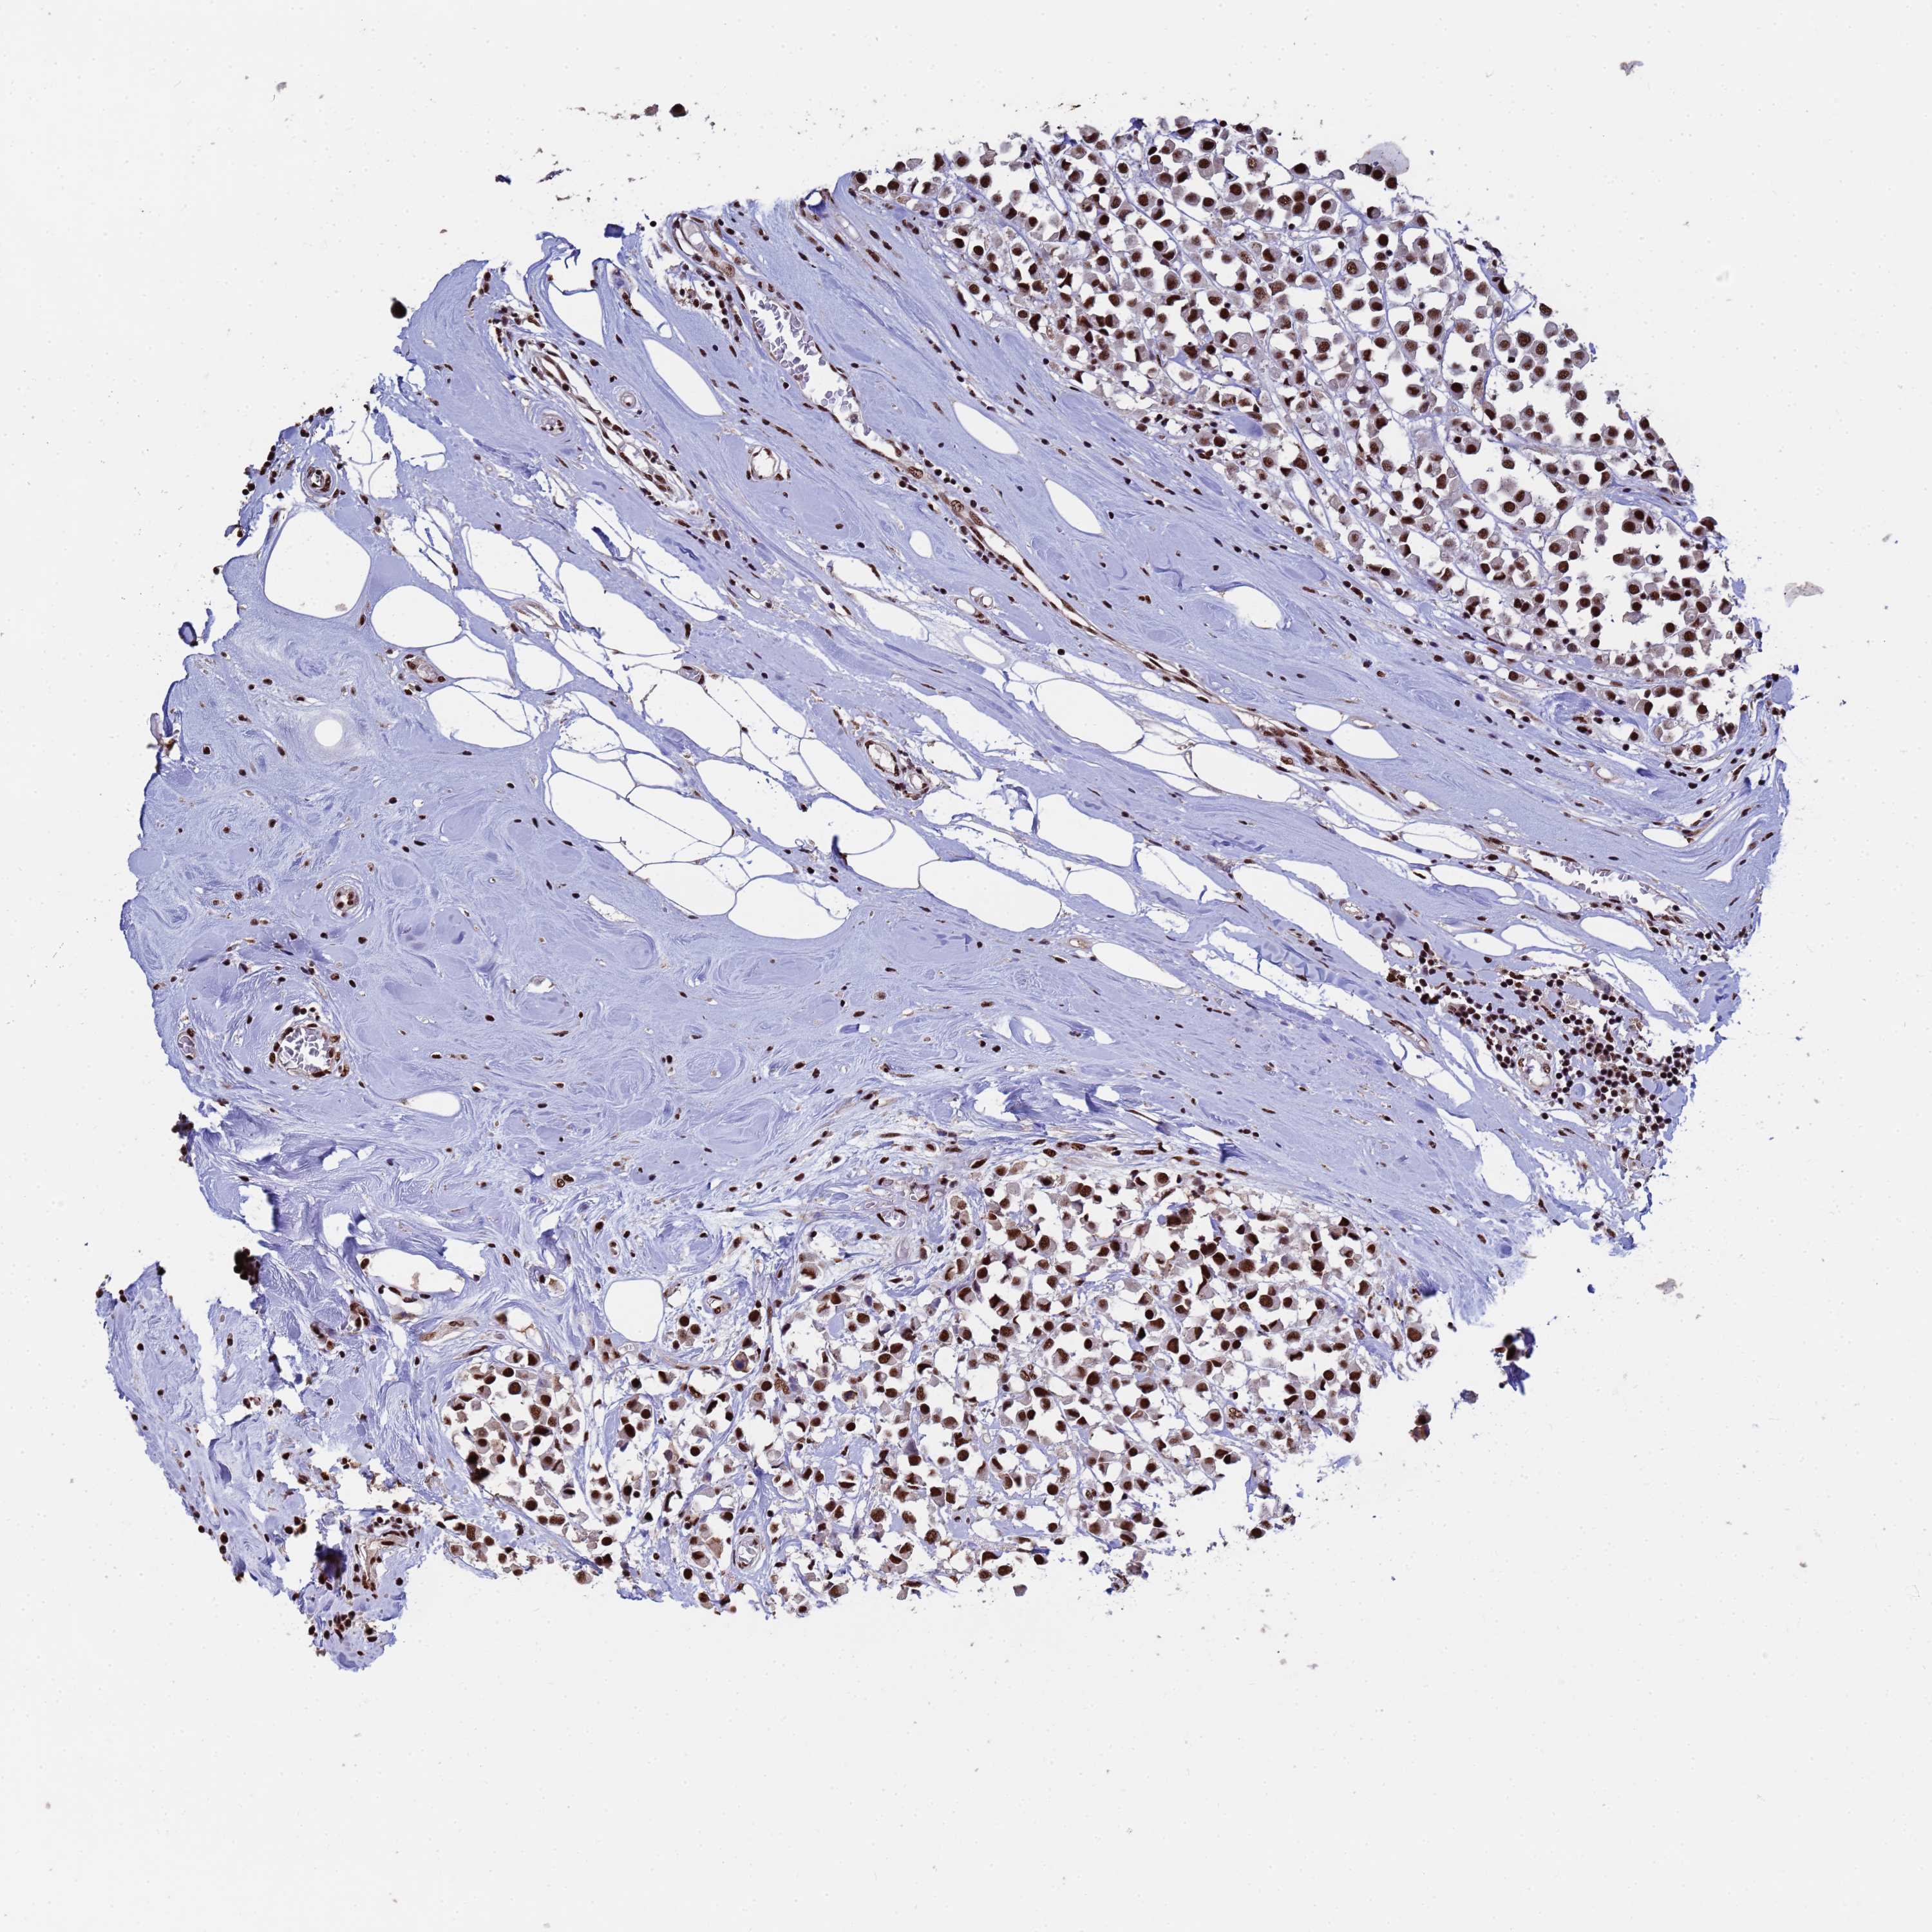

CANCER BREAST CANCER Show tissue menu

BRCA TCGA BRCA VALIDATION PROTEIN EXPRESSION